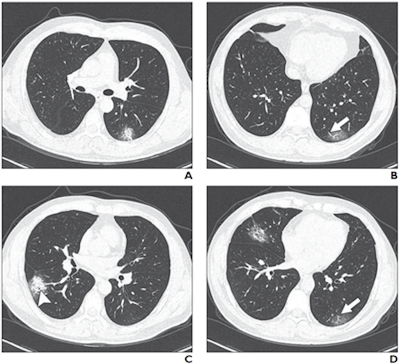

Below:A 63-year-old woman with confirmed COVID-19, severe type. Patient had long-term exposure history to Wuhan and onset symptoms of fever and cough. CT was performed one day after admission. A-D: CT images show bilateral diffuse GGOs and reticulation (arrow, C). All images courtesy of the AJR.